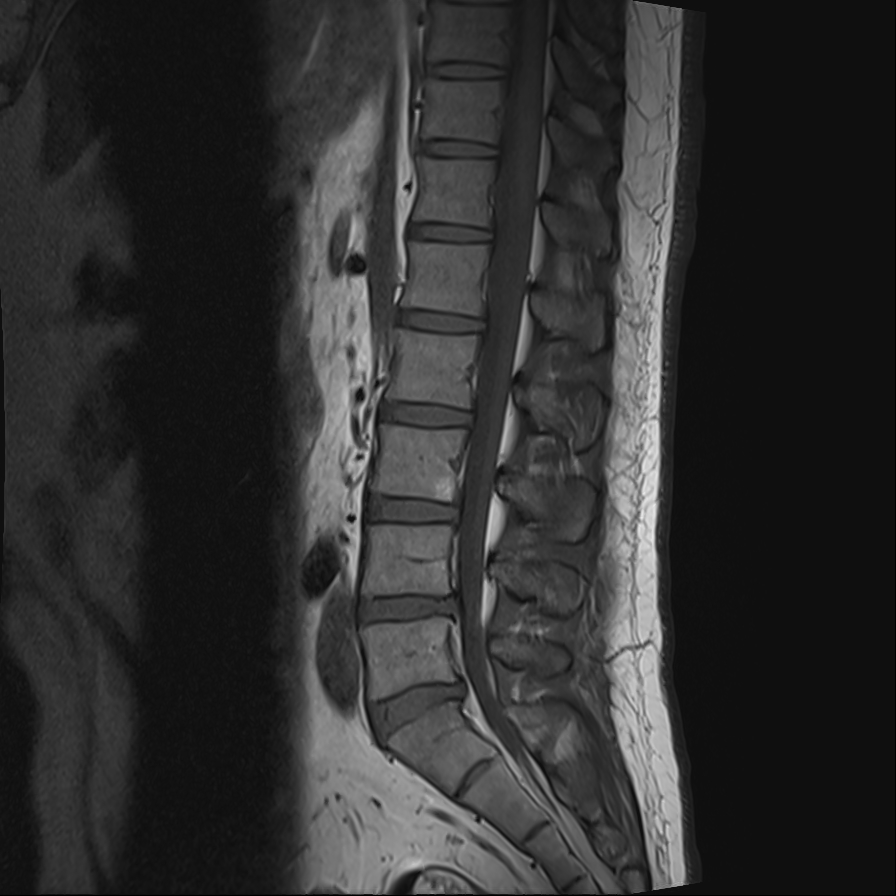

위 사진이 바로 제 허리 사진입니다.

하지만, 분명 병원에 첫 방문했을 당시 4~5번 디스크가 조금 튀어 나오기는 했으나 수술을 요하는 단계까지는 아닌 것 같고 아직 사회활동도 해야 하니 주사를 맞아보고 불가피할 경우 시술로 진행하는 것이 좋겠다고 이야기했었는데 2차례 주사를 맞은 뒤에는 수술 이야기를 꺼내서 신뢰가 가지 않았고, 인터넷을 검색해보니 디스크가 무척 심해서 수술을 한 사람도 수술 후 다리저림 현상으로 고생하고 있다는 이야기가 적지 않아서 수술을 거절했습니다.

정확히는 허리 통증은 사라졌지만 그 후 오른쪽 엉덩이부터 다리까지 이어지는 저림 증상이 계속되고 있는 상태.

여수의 병원에서는 답이 없는 것 같아서 순천에 있는 척추 전문 병원에 들러서 2차례 허리 근육 주사도 맞아봤지만 다리 저림 증상은 여전했고, 병원에서 수술 권유까지 듣게 되었습니다.